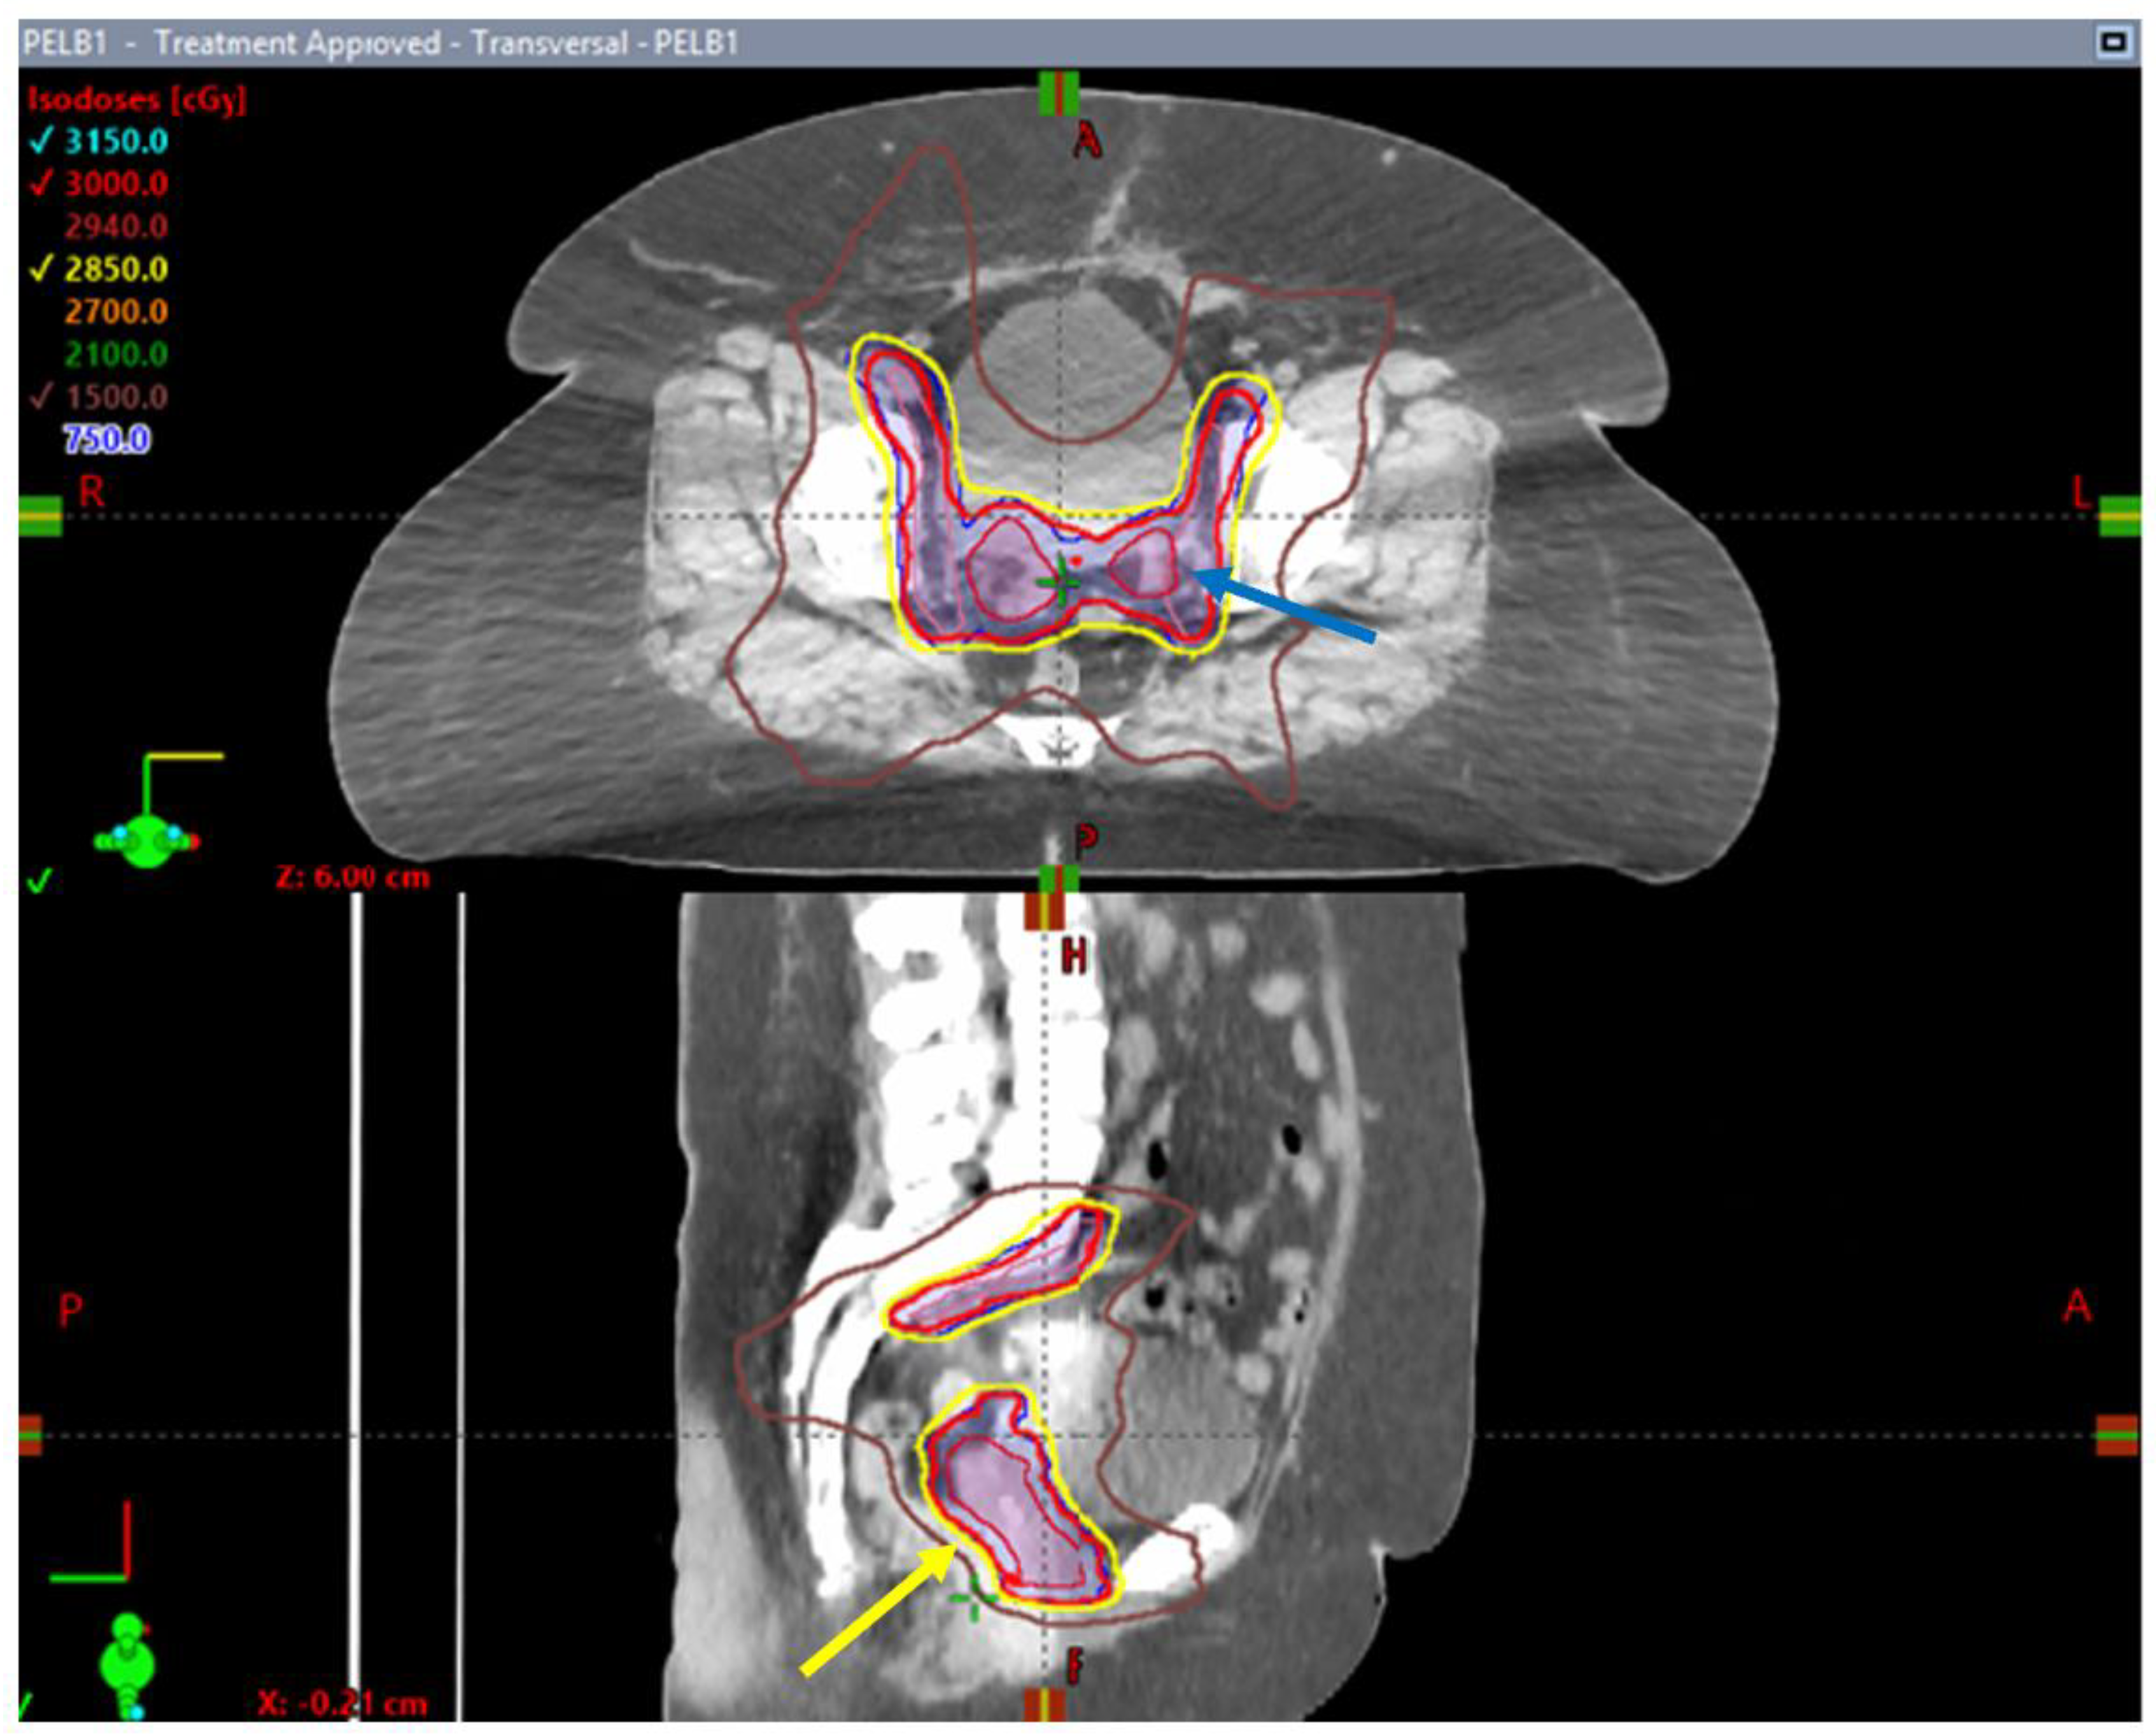

- Gandhi, A.K.; Rastogi, M.; Yadav, U.; Mishra, V.; Srivastava, A.K.; Bharati, A.; Mishra, S.P. A Pilot Study of Moderately Hypo-Fractionated Whole Pelvic Radiotherapy with Concurrent Chemotherapy and Image-Guided High Dose Rate Brachytherapy for Locally Advanced Cervical Carcinoma. Int. J. Radiat. Oncol. Biol. Phys. 2022, 114, S89. [Google Scholar] [CrossRef]

- Mendez, L. Hypofractionated External-Beam RadiOtherapy for Intact Cervical Cancer (HEROICC-Trial): A Feasibility Study; NCT04583254. 2023. Available online: https://clinicaltrials.gov (accessed on 5 May 2023).

- Cantu, D. Phase II Randomized Controlled Trial of Concomitant Chemoradiotherapy with Standard Fractionation Compared to Hypofractionated Concomitant Chemoradiotherapy Followed by Brachytherapy, for Clinical Stage III Cervical Cancer Patients; NCT04070976. 2020. Available online: https://clinicaltrials.gov (accessed on 5 May 2023).

- Tehran University of Medical Sciences Comparison of Clinical Response and Toxicity of Hypo-Fractionated Chemoradiation with Standard Treatment in Patients with Uterine Cervix Cancer; NCT04831437. 2021. Available online: https://clinicaltrials.gov (accessed on 5 May 2023).

- Bacorro, W.; Baldivia, K.; Dumago, M.; Bojador, M.; Milo, A.; Trinidad, C.M.; Mariano, J.; Gonzalez, G.; Sy Ortin, T. Phase 1/2 Trial Evaluating the Effectiveness and Safety of Dose-Adapted Hypofractionated Pelvic Radiotherapy for Advanced Cervical Cancers INeligible for ChemoTherapy (HYACINCT). Acta Oncol. 2022, 61, 688–697. [Google Scholar] [CrossRef] [PubMed]

- Prasartseree, T.; Dankulchai, P.; Sittiwong, W.; Thephamongkhol, K. HYPOCx-iRex (TCTR20210812003) A Phase II RCT: 44 Gy/20F vs. 45 Gy/25F CCRT in Cervical Cancer: Six-Month Post-RT Update. Int. J. Radiat. Oncol. Biol. Phys. 2023, 117, S41. [Google Scholar] [CrossRef]